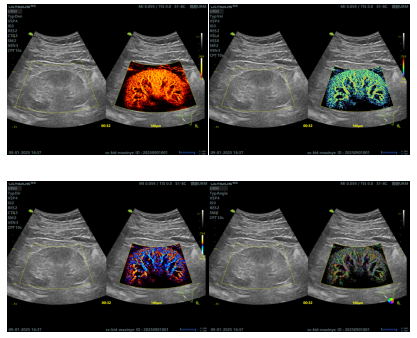

3月12日至14日,2026年第17届亚洲超声医学与生物学联合会大会(AFSUMB)在越南岘港召开。超声诊疗科宋璇医生首次受邀参加本次大会,并作了题为Super-Resolution Ultrasound Imaging of Renal Microvascular Rarefaction and Remodeling in Chronic Kidney Disease—a preliminary study的大会发言,受到与会专家的一致好评。

超分辨显微超声成像技术是最新的超声医学技术,突破了传统超声分辨率的局限,能够显示数十微米级血管,为肾病疾病的诊断、疾病监测和治疗效果评估带来了新的机遇,其作为超声影像领域的前沿突破,在肝脏、甲状腺、乳腺、肌肉神经等多个器官的疾病诊断中也有重要的潜在临床应用价值。